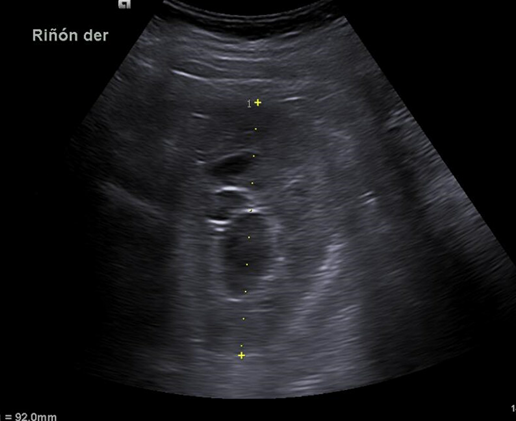

Hallazgos ecográficos

Riñón derecho 9,9 cm con morfología y ecogenicidad conservada. Presenta hidronefrosis grado III. No se identifica causa obstructiva.